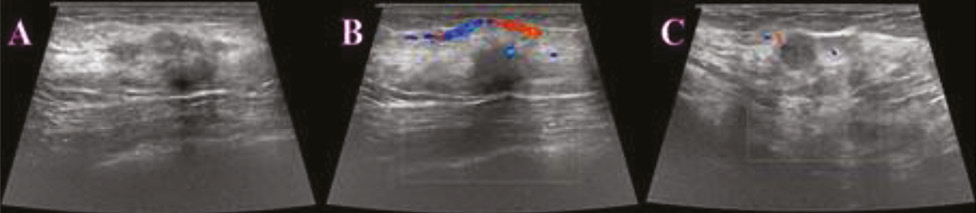

Виконано УЗД МЗ на діагностичному ультразвуковому приладі LOGIQ S7 Expert, GE Ultrasound Korea Ltd, Республіка Корея. У правій МЗ на 1 год визначалося гіпоехогенне гетерогенне новоутворення неправильної форми з нечіткими нерівними контурами, розміром 29×23×18 мм, з ознаками локусів інтранодулярного кровотоку при кольоровому доплерівському картуванні (КДК). Поруч візуалізувалися аналогічної структури: 3 новоутворення розміром 4; 5 та 8 мм, які не виявлялися на площинній мамографії через високу щільність паренхіми (рис. 2). У правій пахвовій ділянці лімфатичні вузли розміром до 23×17 мм, з гіпоехогенним, нерівномірно потовщеним кірковим шаром до 5 мм.

Рис. 2. УЗД правої МЗ. На 1 год — гіпоехогенне гетерогенне новоутворення неправильної форми з нечіткими нерівними контурами, з ознаками інтранодулярного кровотоку при КДК (a, b). Пухлинні новоутворення № 3, які не візуалізувалися на площинній мамографії (c, d)